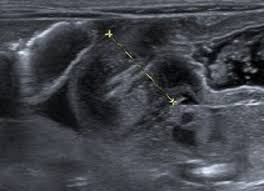

Caracterizada por un engrosamiento anormal del músculo pilórico, lo que lleva a una obstrucción de la salida gástrica. Esta condición es una causa común de vómitos no biliosos en lactantes y generalmente se presenta entre las 2 y 12 semanas de vida.

El diagnóstico se realiza principalmente mediante ecografía, que muestra un alargamiento constante y un engrosamiento de la pared del píloro, con una longitud del canal pilórico superior a 18 mm y un grosor muscular de al menos 4 mm.

Ejemplos de estenosis pilorica hipertrofica infantil.